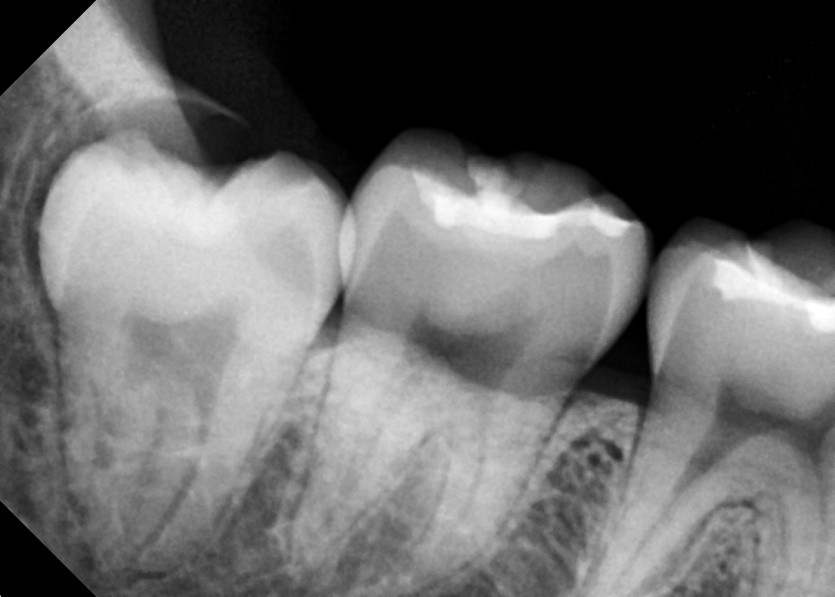

#18,48 사랑니 발치

구강 외과 전문의가 당일 발치했습니다.